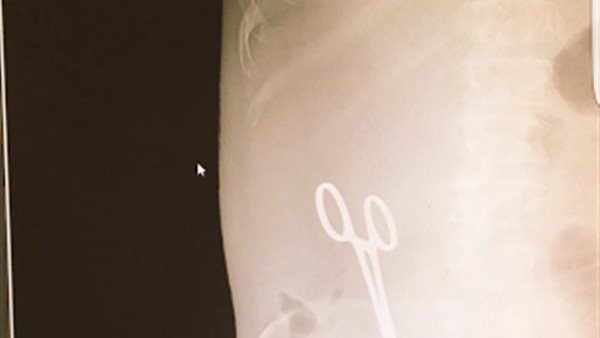

أصدرت المديرية العامة للشئون الصحية بمنطقة حائل، بالمملكة العربية السعودية، اليوم الجمعة، بيانًا اعتذرت فيه عن واقعة نسيان "مقص" داخل بطن مريض أثناء عملية جراحية له.

وأكدت صحيفة "عاجل" السعودية، أن الطبيب الوافد صاحب الواقعة، هو مصري الجنسية، وجدير بالذكر، أن إدارة مستشفى الملك خالد بحائل، حققت مع الطبيب المصري، إثر اتهام مريض له بنسيان مقص طبي في بطنه، بعد عملية أجراها له حيث أحس المريض بألم شديد في بطنه بعد العملية، وقام بعمل أشعة وتبين وجود المقص؛ إثر العملية السابقة.